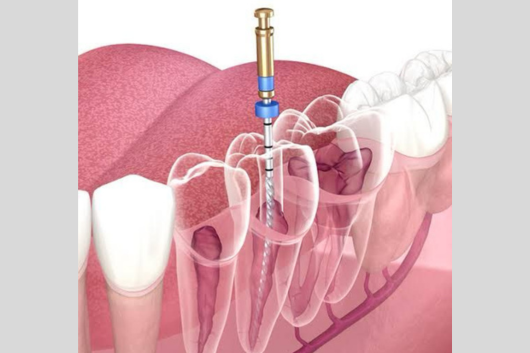

Single sitting Root canal Treatment

Tooth decay, when left untreated, can lead to pulp infection, causing pain and discomfort. The pulp — the soft tissue inside the tooth — contains blood vessels and nerves. Our single sitting root canal treatment removes the infected tissue and replaces it with a filling material to preserve the tooth. The best part? The entire procedure is pain-free and completed in just one session, relieving you from further complications.